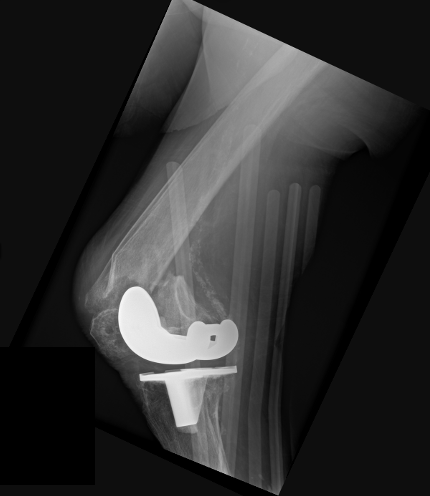

An 86-year-old male after a low-energy fall onto the right knee with a periprosthetic distal femur fracture above a TKA. These cases are getting more common, and the real challenge is not whether to operate—it’s choosing the construct. Nail? Plate? Dual plate? Nail-plate combo? Or do you skip fixation and replace it? For me, the decision tree starts with 3 questions: 1. Is the femoral component stable? 2. Is the femoral box actually nail-compatible? 3. Is the distal segment/bone stock strong enough for single-implant fixation? What would you do here? @orthobullets @medbullets orthobullets.com/Site/Cases/Vie…

Jan Szatkowski tweet mediaJan Szatkowski tweet mediaJan Szatkowski tweet media